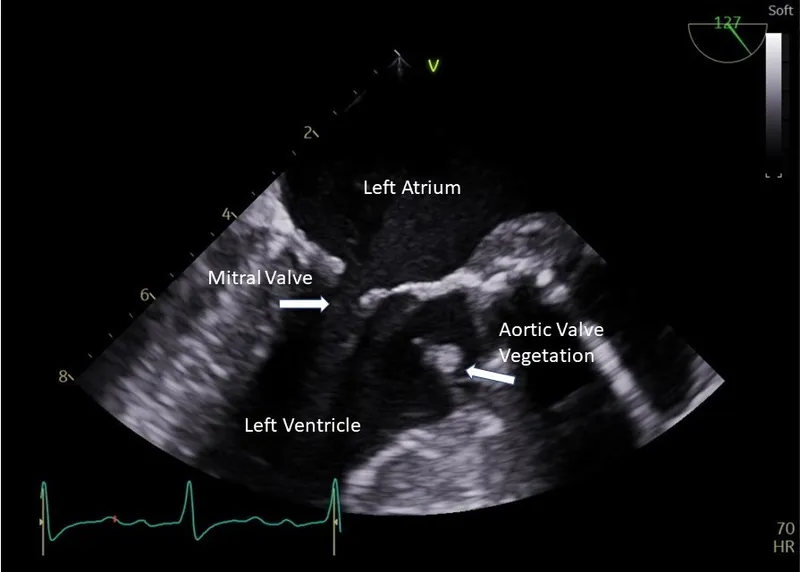

- Echocardiogram: Evidence of endocardial involvement (vegetation, abscess, new valvular regurgitation).